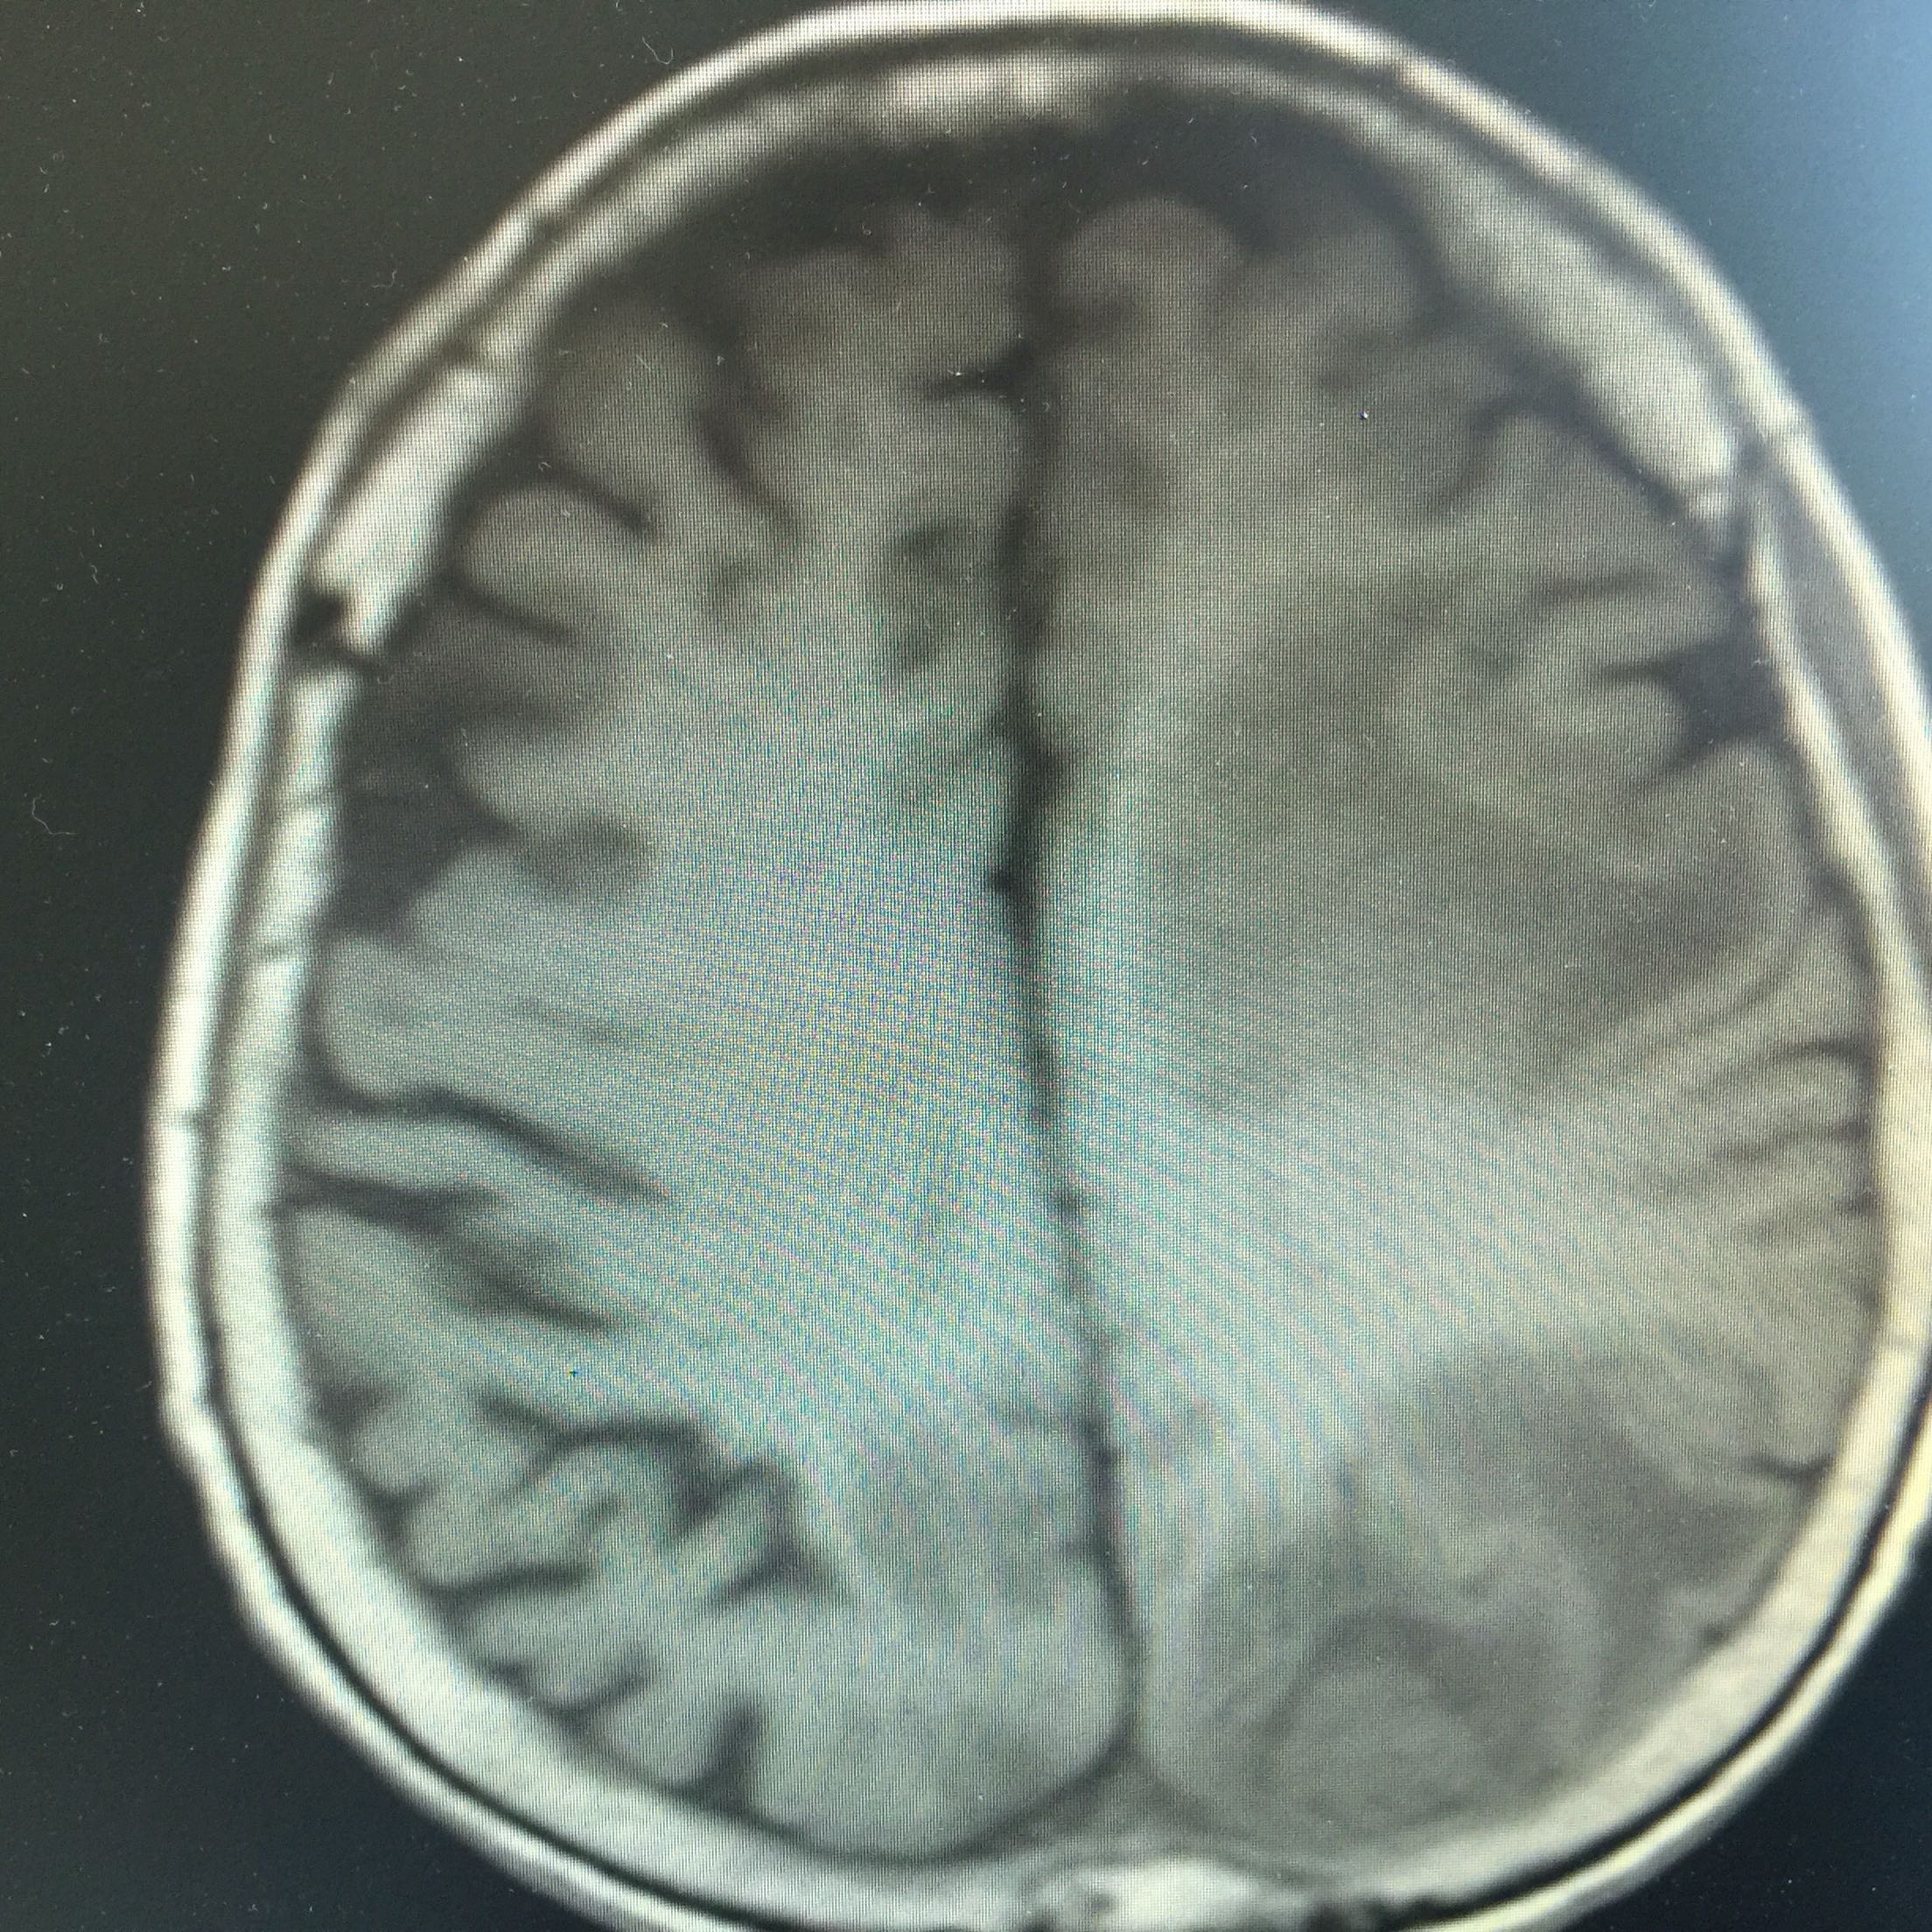

1.女,81岁,以“右侧肢体无力3天”入院。 2.现病史:3天前无诱因出现右侧肢体无力,右上肢抬举费力,右下肢步行拖拉,无抽搐,无意识障碍! 3.既往史:2016年肺穿刺活检,免疫组化为腺癌!已合并第五、六椎体转移、左肾上腺转移,行灌注介入治疗。

左肺腺癌 骨转移、双肺门及纵膈淋巴结转移、左肾上腺转移、脑转移! 治疗:对称、支持治疗!